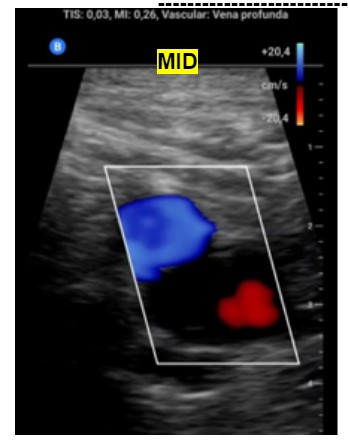

Ante la sospecha de Trombosis venosa profunda realizamos ecografía de compresión venosa de miembros inferiores detectando la falta de colapsabilidad de la femoral común y femoral superficial del miembro inferior derecho, cosa que no pasaba en el izquierdo.